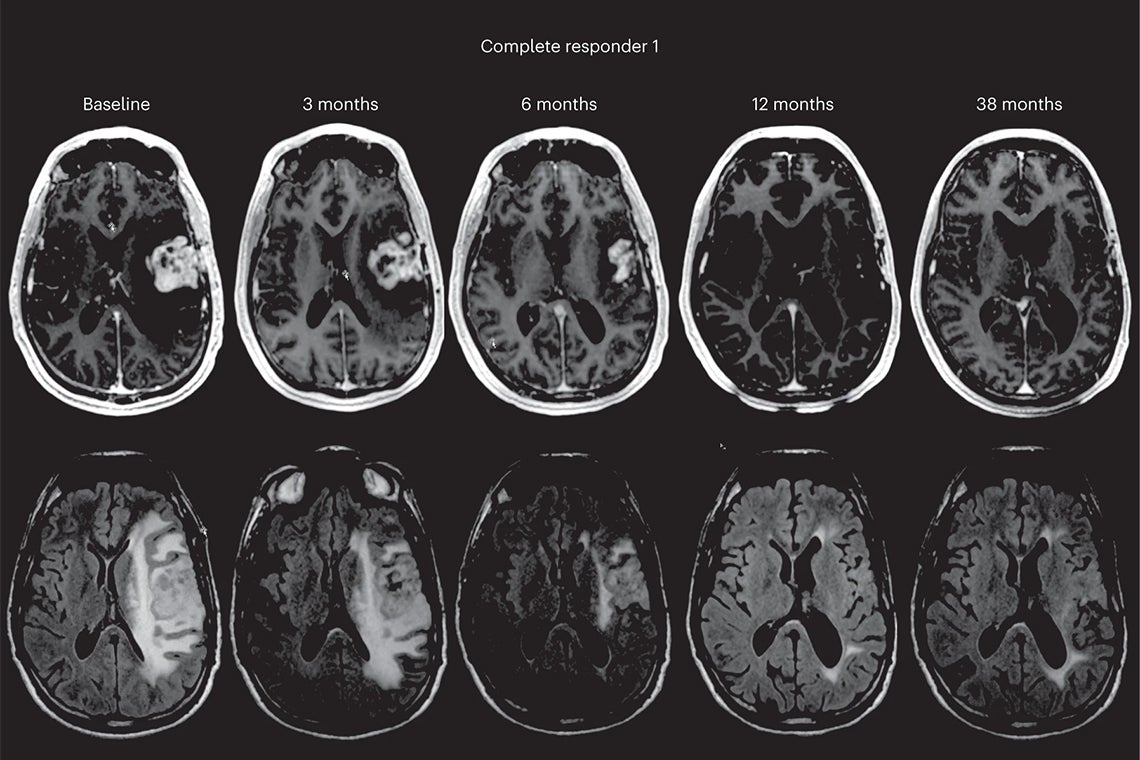

Imaging from the study following infusion of the oncolytic immunotherapy DNX-2401 (supplied image)

“Over half of our patients achieved a clinical benefit – stable disease or better – and we saw some remarkable responses with tumours shrinking, and some even disappearing completely. Three patients remain alive at 45, 48 and 60 months after starting the clinical trial.”